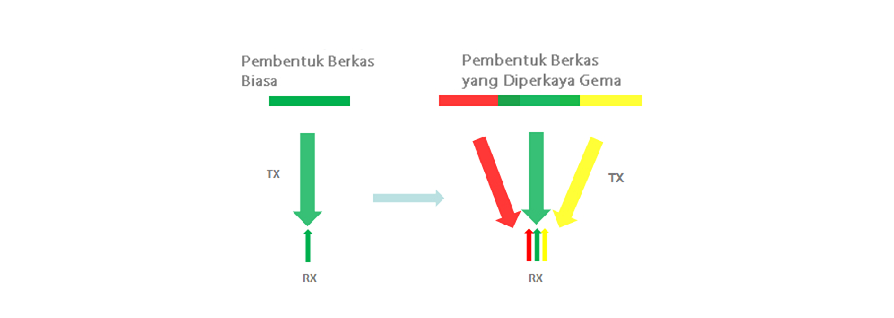

Pembentukan Berkas yang Diperkaya Gema

Pembentukan berkas yang diperkaya gema memungkinkan penggunaan sinyal gema yang biasanya ditolak pada berkas berdekatan untuk membentuk satu berkas pencitraan yang lebih halus dan lebih kuat, sehingga memberikan resolusi gambar ŌĆśtidak fokusŌĆÖ yang lebih baik dan penetrasi gambar yang lebih dalam.